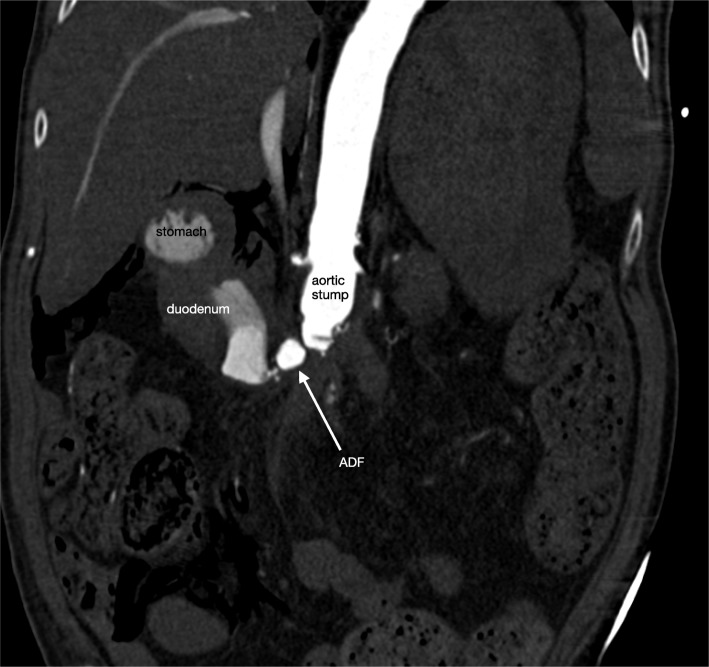

Fig. 1.

CTA abdomen showing massive extravasation of blood due to a secondary ADF

CTA demonstrating massive extravasation of blood through the aortic stump into the duodenum, due to a secondary ADF (marked with an arrow).